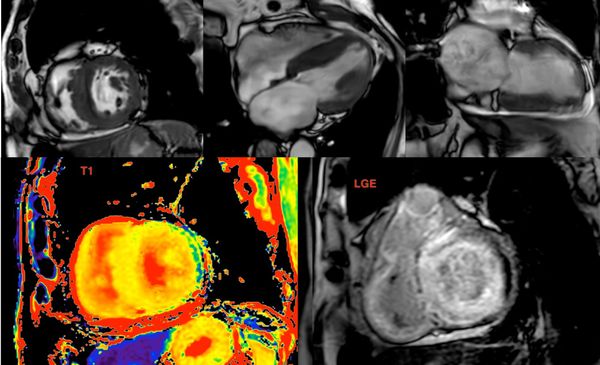

The Value of Extracellular Volume (ECV) in ATTR - Transthyretin Amyloidosis

Cardiac MRI is a useful tool to diagnose amyloidosis. T1 mapping has become a mainstay, both native and ECV measurements. ECV measurement can now help quantify the amyloidosis burden and may help guide treatment based on how the ECV responds to specific treatment measures.